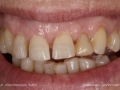

As Facetas Cerâmicas (lentes de contacto dentárias ou laminados), permitem corrigir da maneira mais estética e conservadora possível, problemas de forma e tamanho, côr e posição dos dentes, bem como substituir restaurações antigas e inestéticas.

São aderidas químicamente ao esmalte dentário de uma forma permanente, com o objectivo de melhorar a estética dos nossos pacientes.